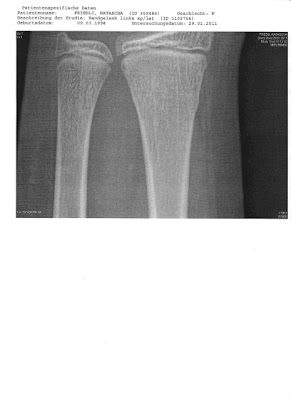

es ist zum Glück nicht komplett durchgebrochen... am rechten Knochen aussen sieht man einen Hubel... und da ist der Knochen angebrochen...